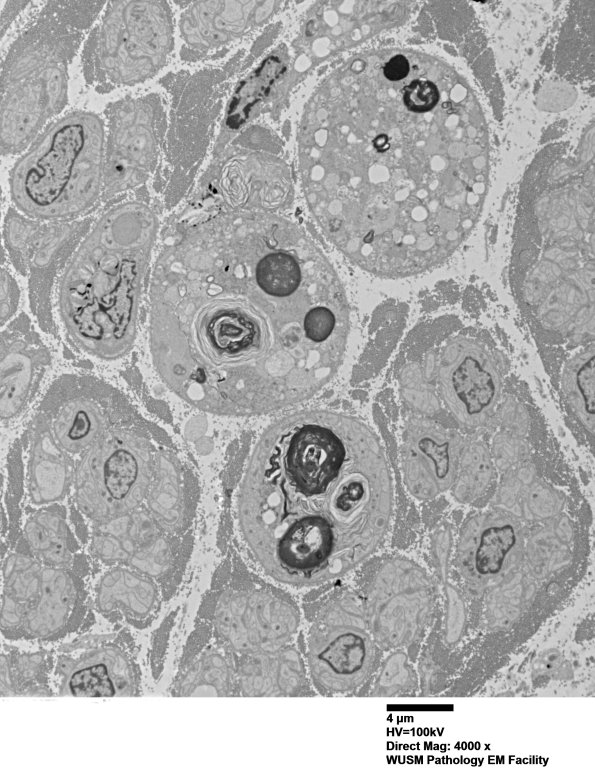

Low magnification view showing the loss of normal structures and the variation in appearance from one degenerating axon to another.